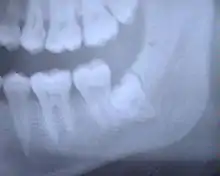

Características radiográficas

Aumento do espaço do ligamento periodontal visível nos molares mandibulares

- Aumento do espaço do ligamento periodontal

- Alterações no trabeculado ósseo

- Cálculos pulpares

- Reabsorção radicular

- Alteração de continuidade da lâmina dura